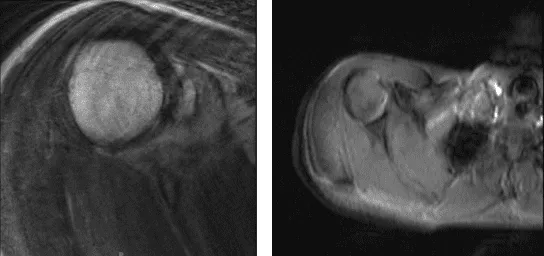

Dos semanas después de la operación, se realizó una resonancia magnética. La resonancia magnética del hombro derecho mostró esguince articular AC y tendinitis calcifica sospechosa del tendón supraespinoso.

Se recomienda repetir la correlación con radiografías o TAC para una evaluación definitiva. Se revisó la resonancia magnética del hombro izquierdo, se encontró desgarro parcial focal de bajo grado del tendón supraespinoso anterior y bursitis subdeltoidea subacromial leve.

MRI-3T Hombro derecho sin contraste

MRI-3T Hombro Izquierdo sin contraste